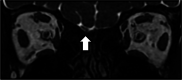

Results: Among 189 patients included in the long COVID sample, 48 (25.3%) had sleep-related symptoms. Insomnia was reported by 42 patients (22.2%), and excessive sleepiness (ES) was reported by 6 patients (3.17%). Four patients with ES were evaluated with polysomnography and test, multiple sleep latencies test, and actigraphic data. Two patients had a diagnosis of central hypersomnia, and one had narcolepsy. A history of steroid use was related to sleep complaints (insomnia and excessive sleepiness), whereas depression was related to excessive sleepiness. We observed a high prevalence of cognitive complaints in these patients.